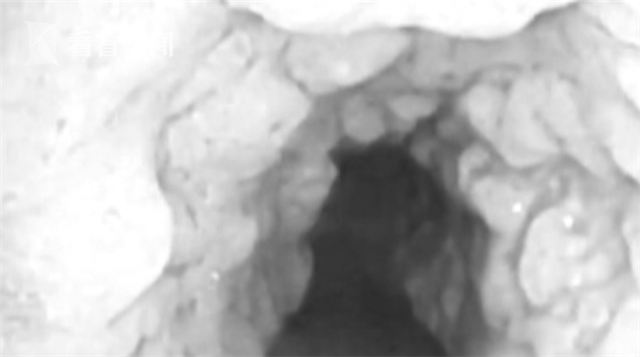

最近,扬州市市民张师傅经常感觉呼吸困难,他到医院进行体检,结果却让他吓了一跳:他的气管内壁里竟然长满了“小牙齿”。

可最近,呼吸困难的症状愈来愈严重,张师傅赶紧回来到苏北医院检查。医生通过气管镜检查发现,张师傅的气管内壁从上到下长满了类似牙齿的突起物。

“当时我们准备做活检,做个组织切片,却发现这个东西像个牙齿一样坚硬,根本夹不动。”苏北医院呼吸科主任医师朱湘平介绍说。

朱医生介绍,这种病叫骨化性气管支气管病。1857年,医学界首次发现此种疾病。患者气管内长出很多1到10毫米的结节,伴有咳嗽、 咳痰、血丝痰等症状。

骨化性气管支气管病是一种罕见的疾病,目前这一病例国外发现约380例,国内还不到10例。

它是一种良性疾病,但一旦病人结节增多,气管就狭窄拥堵,病人就会有呼吸困难。